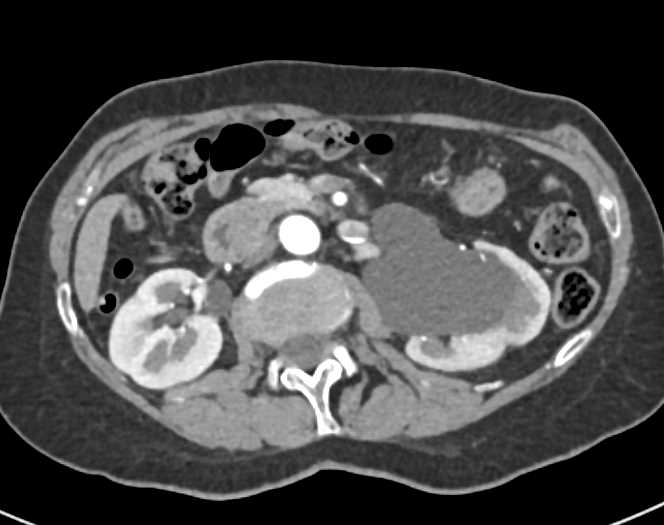

Acute Pyelonephritis Right Kidney